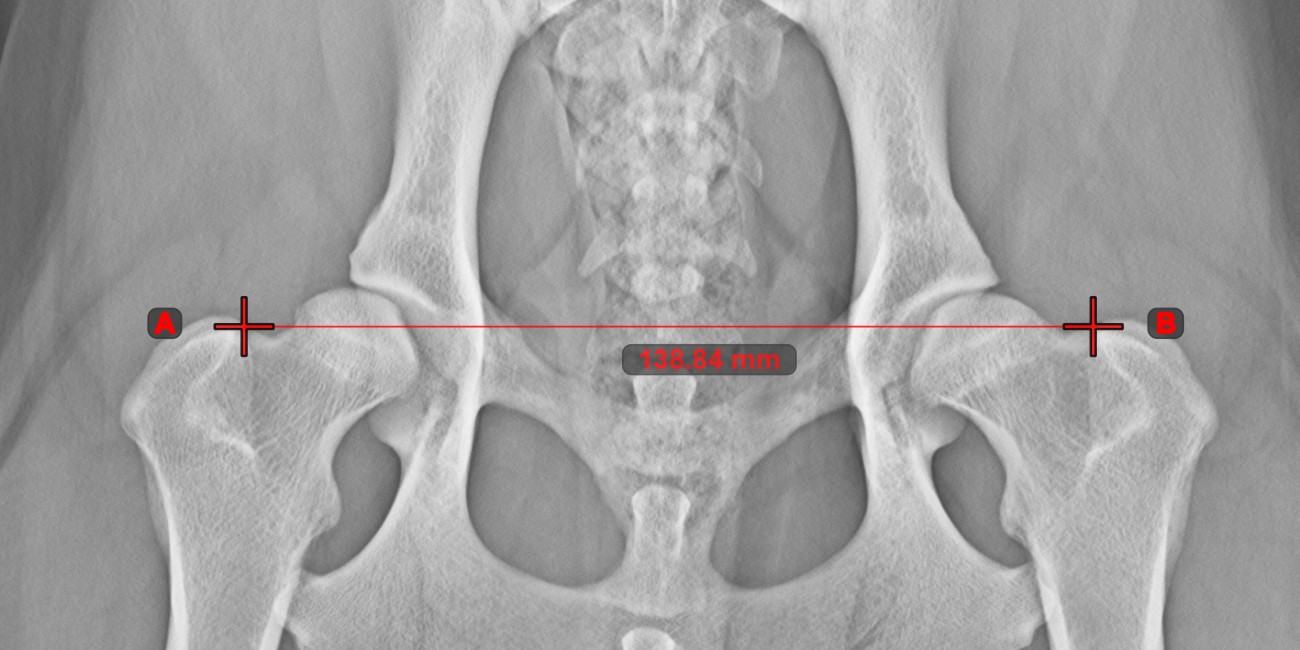

Line Measurement¶

Select the Line Measurement

tool and assign it to one of the available mouse buttons. Place the start and end points on the scene or select them from already existing points on the image. The distance between the two points will be automatically

calculated by using the default calibration data, or the recalibrated data by the length calibration measurement.

Modify the start and end point by using the Select/Move Item

tool. The distance between the two points will be automatically recalculated.